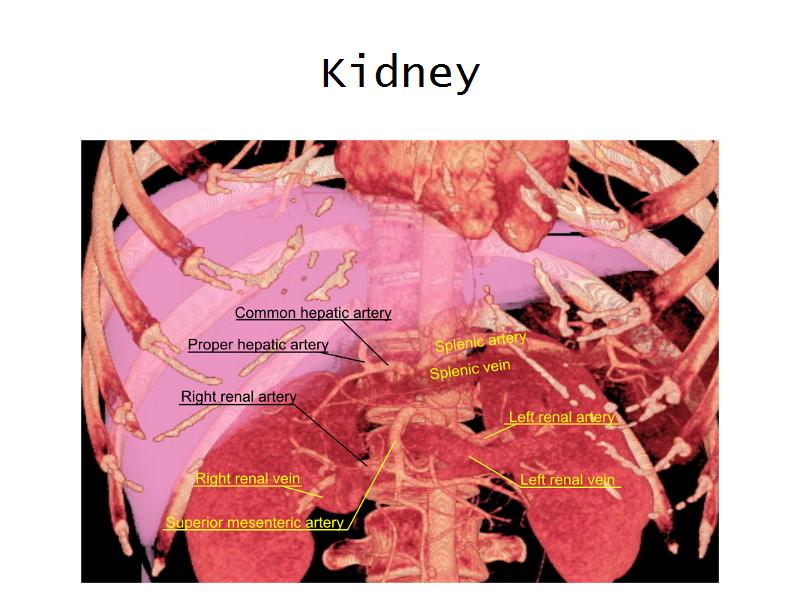

- Kidney

- G3: Adrenal glands = superior poles of the kidneys

- Slide 76: Kidney